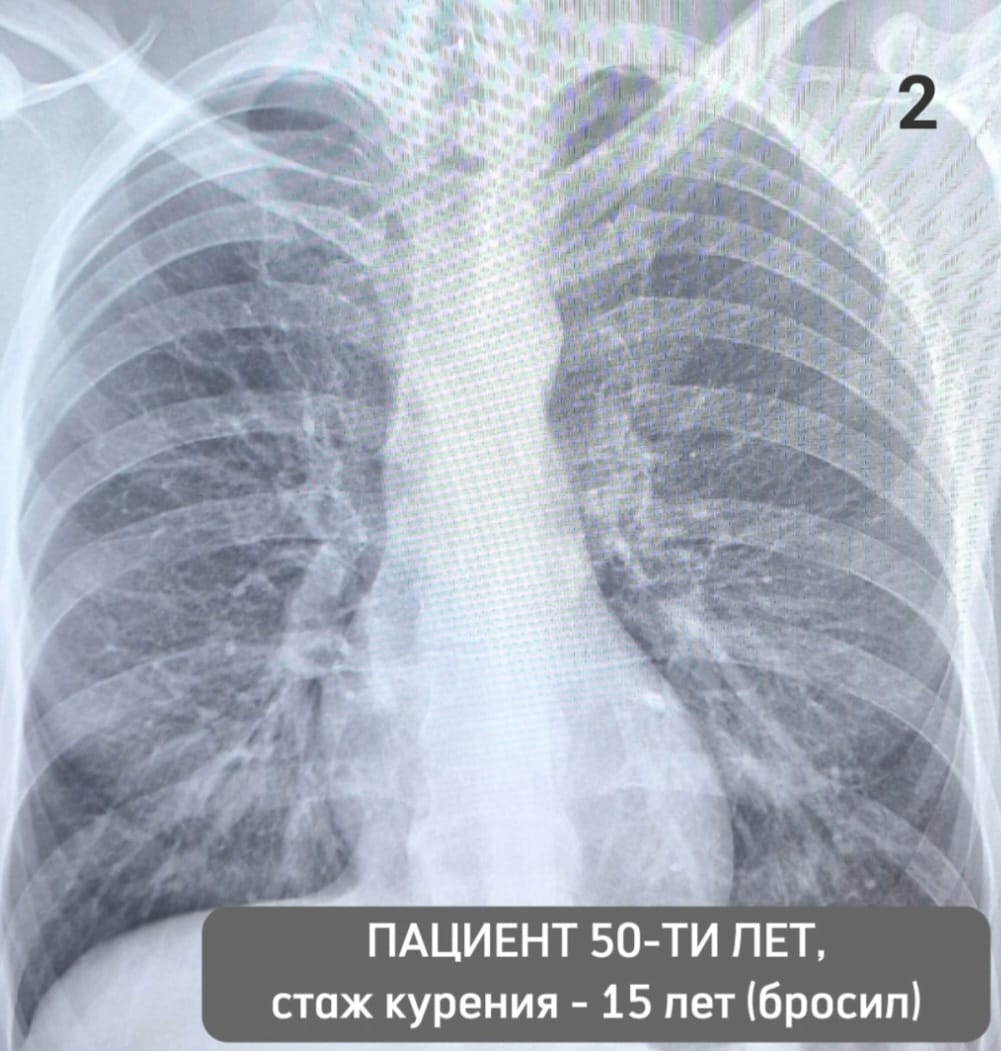

Врачи напоминают: не бывает безопасного курения. Вред от обычных или электронных сигарет, вейпа или кальяна одинаков: курильщики в любом случае потребляют отравляющие и канцерогенные вещества. Представляем два снимка: на одном - лёгкие курильщика с 25-летним стажем, на втором – мужчины, который курил 15 лет, а потом бросил.

«Ренгенографию прошли мужчины-ровесники. Им по 50 лет. Первый не может, не задыхаясь, подняться на 3 этаж, второй – уже 5 лет ходит в пешие походы по самым живописным уголкам страны, - рассказал врач-рентгенолог поликлиники №5 Челнов Рамзиль Гильметдинов. – Один пациент отказался от вредной привычки и теперь дышит полной грудью, другой - страдает хроническим бронхитом, пневмосклерозом, одышкой, имеет нарушение сердечного ритма».